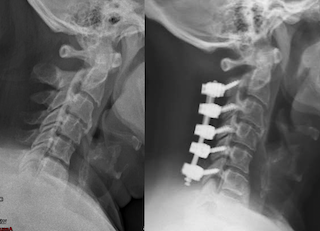

X-ray images of a neck showing a before and after comparison; the right side displays a cervical spine with surgical hardware indicating spinal fusion.

• Stabilizes the spine using screws, rods, and bone graft

The affected vertebrae are stabilized using screws and rods placed in the spine. Bone graft is placed to allow the vertebrae to fuse together over time.

Fusion prevents abnormal movement between vertebrae and helps maintain spinal stability after decompression.